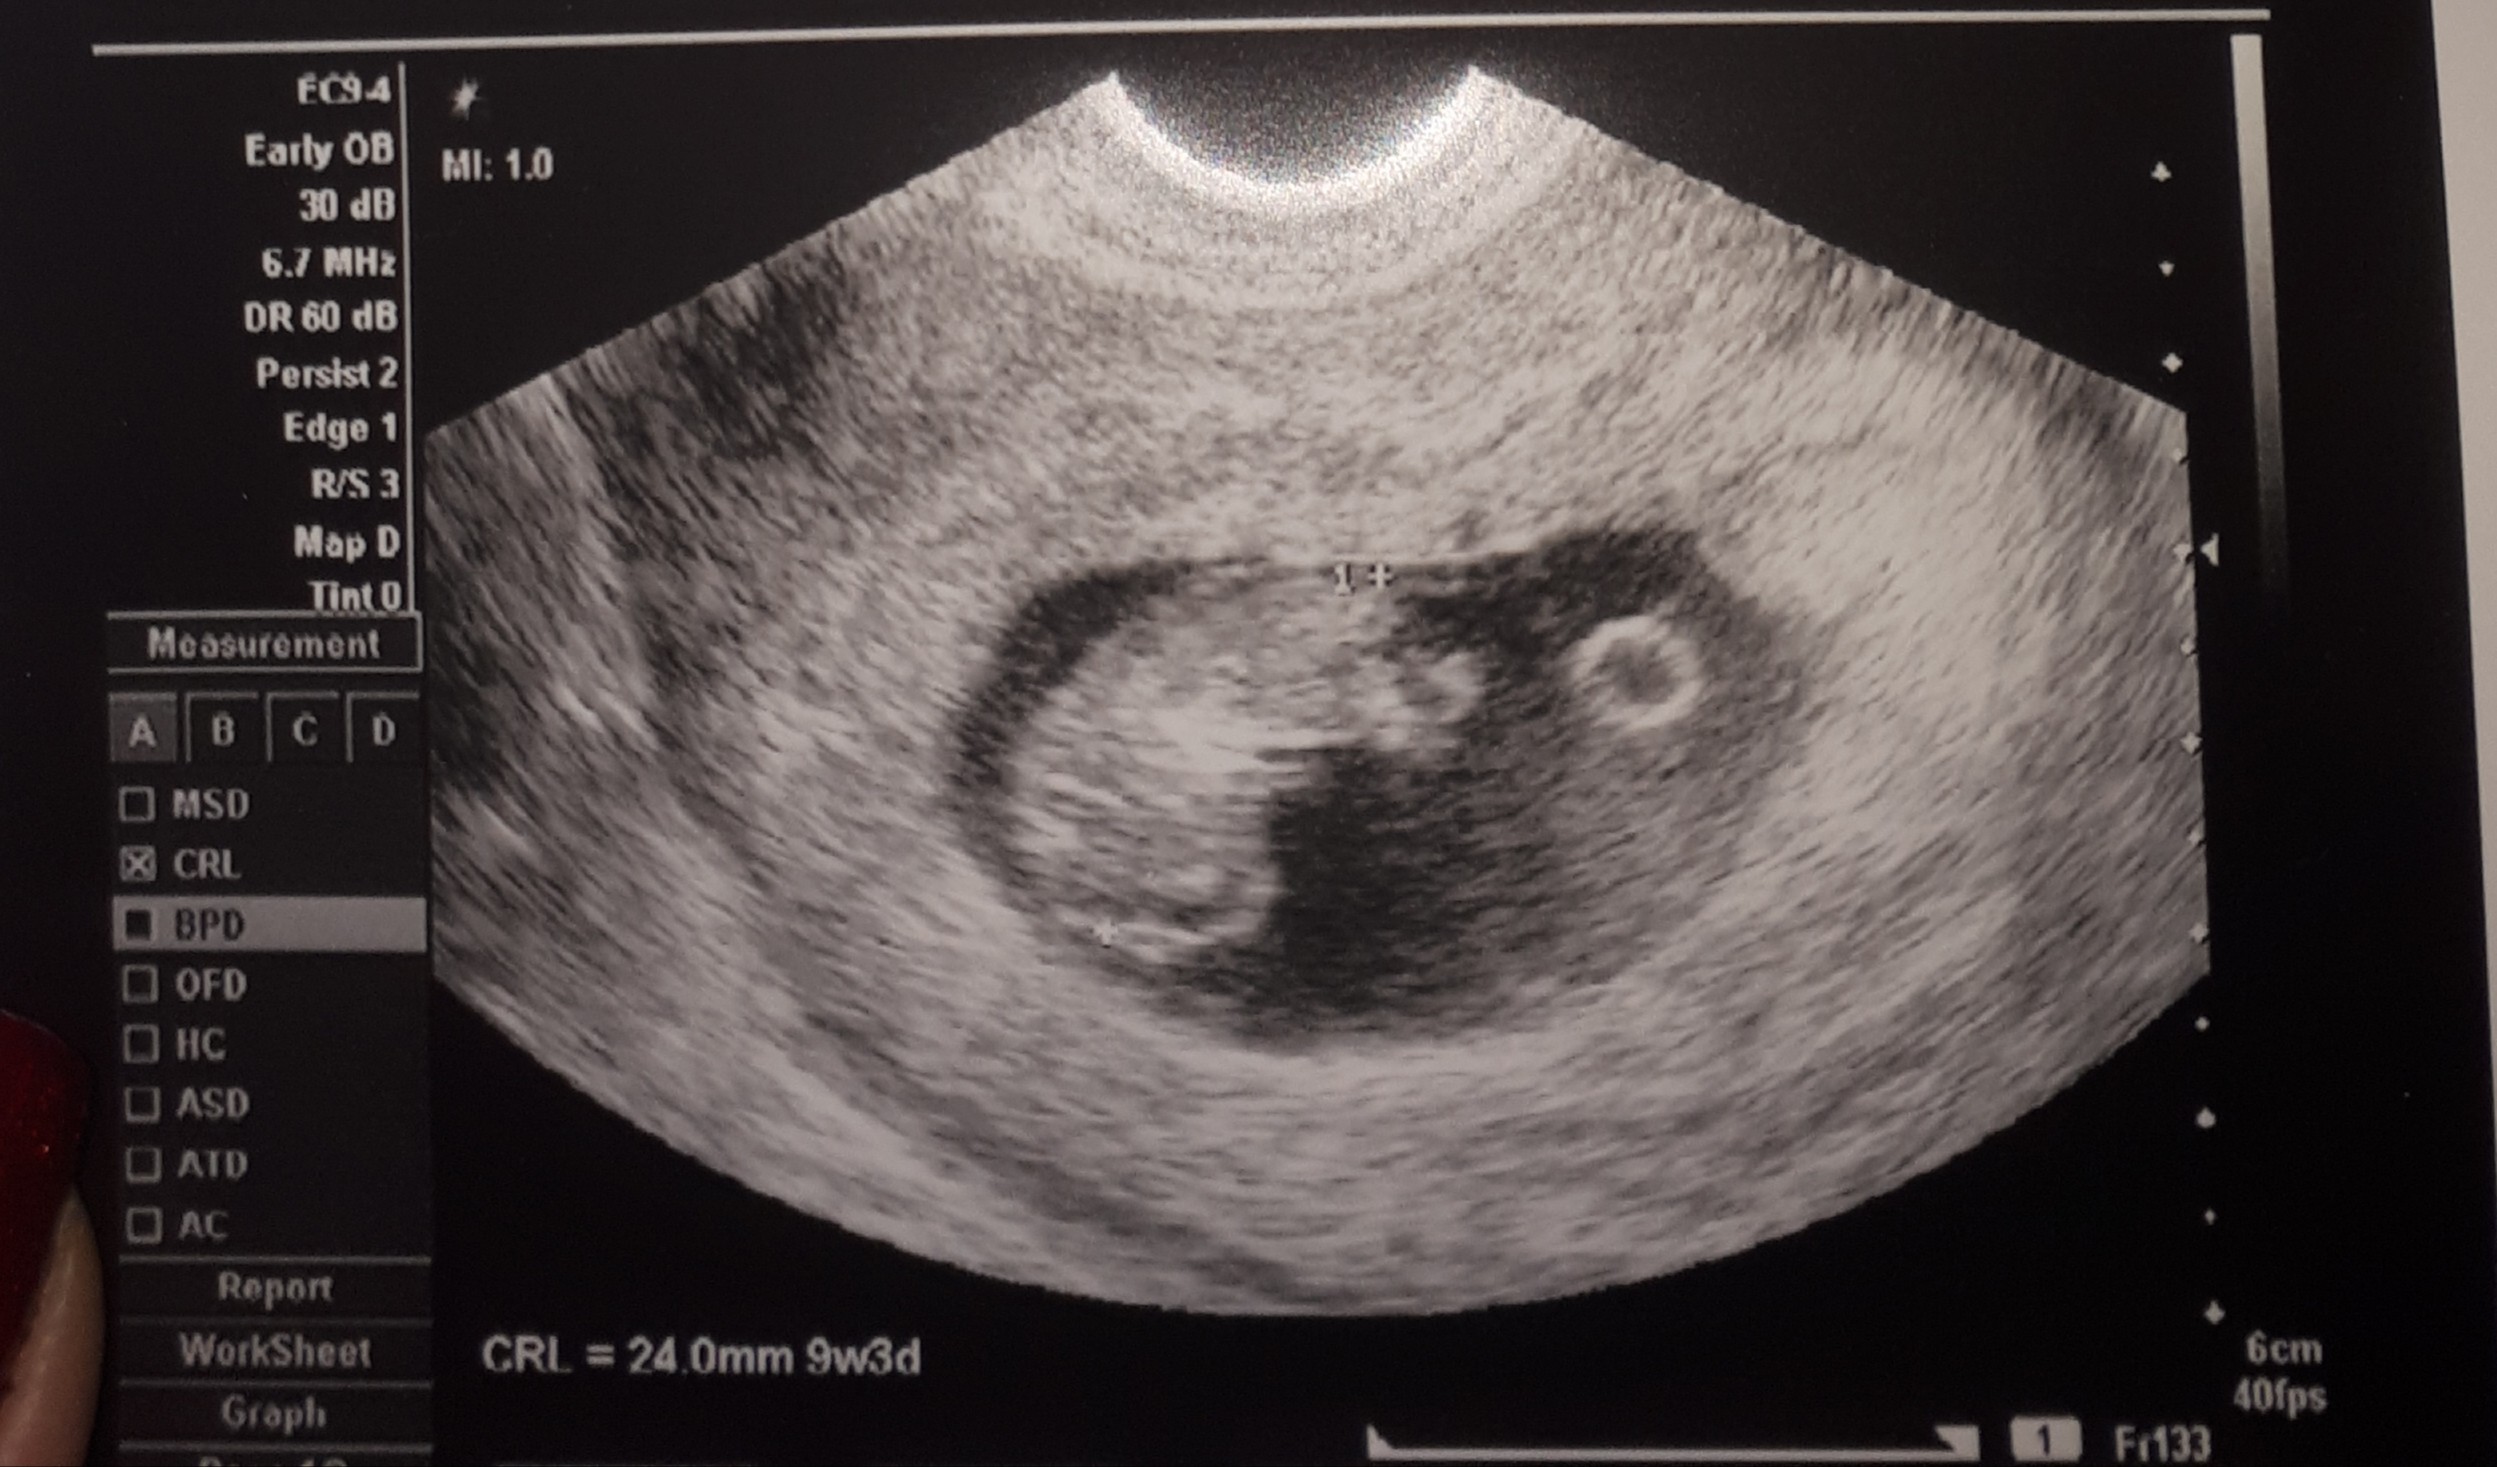

Hej dziewczyny :) wczoraj miałam druga wizytę :) 9t2d dzidzia ładnie rosnie ma już 2,3 cm co idealnie odpowiada terminom z OM. Wychodzi 2.09.2020 :) widać raczki i nóżki, skacze już maluch tam w środku :)

IMG_8746.JPG